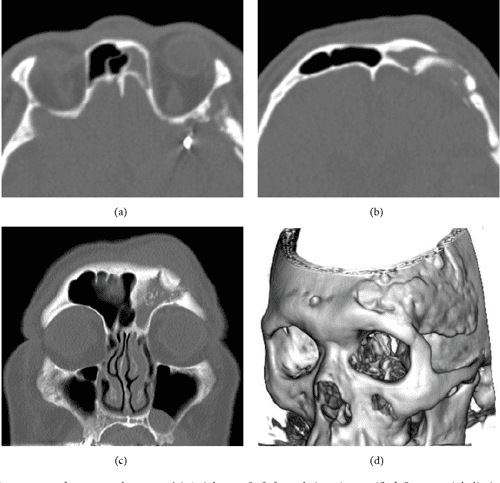

What are CT findings suggestive of sinusitis?

The CT findings suggestive of sinusitis are sinus opacification, air-fluid levels, sinus wall displacement, and 4 mm or greater mucosal thickening. Culture and biopsy are indicated for chronic bacterial and fungal sinusitis.